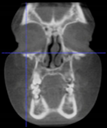

Three points determined the Acta plane: O, F right (FR), and F left (FL) (Table 2). Point O is the midpoint between the most craniodorsal point of the dorsum Sella and the most posterior dorsal point of the Basion in the midsagittal plane (Figure 1). Both points F are a result of the intersection between two lines: the line that connects the most inferior points of the lower orbital margins, right and left, and a line perpendicular to this line that runs through the most external points of the orbital margins, right and left (Figure 2). The new transverse reference plane, the Acta plane (Figure 2), is created by connecting the O-point (Figure 1) with FR and FL (Figure 2).

Figure 2.

(A) Construction of the F-points (right and left), frontal view. The F-points are originated from the intersection between the line connecting points A (the most inferior point of the lower orbit) and the perpendicular line to it that passes through points B (most external/lateral point of the Orbita). (B) Transverse view of the ACTA plane.